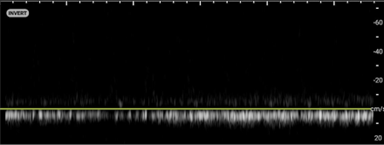

Image 3. Color Doppler demonstrating intratesticular flow toward and away from the probe.

In your first image (Image 1), you realize there is no flow with color Doppler. Additionally, you find a torsed cord complex (Image 2), also known as the “corkscrew sign.” You consult Urology who is busy in the operating room with another case. You decide to perform a manual detorsion due to your concern for testicular atrophy and risk of infertility. Using the open book technique, you get relief of pain and return of vertical positioning of the testicle after two rotations. On your repeat testicular POCUS with color Doppler you obtain these images (Images 3 and 4), which demonstrate venous and arterial flow throughout the testicle. The cord is now untwisted and appears linear in orientation.